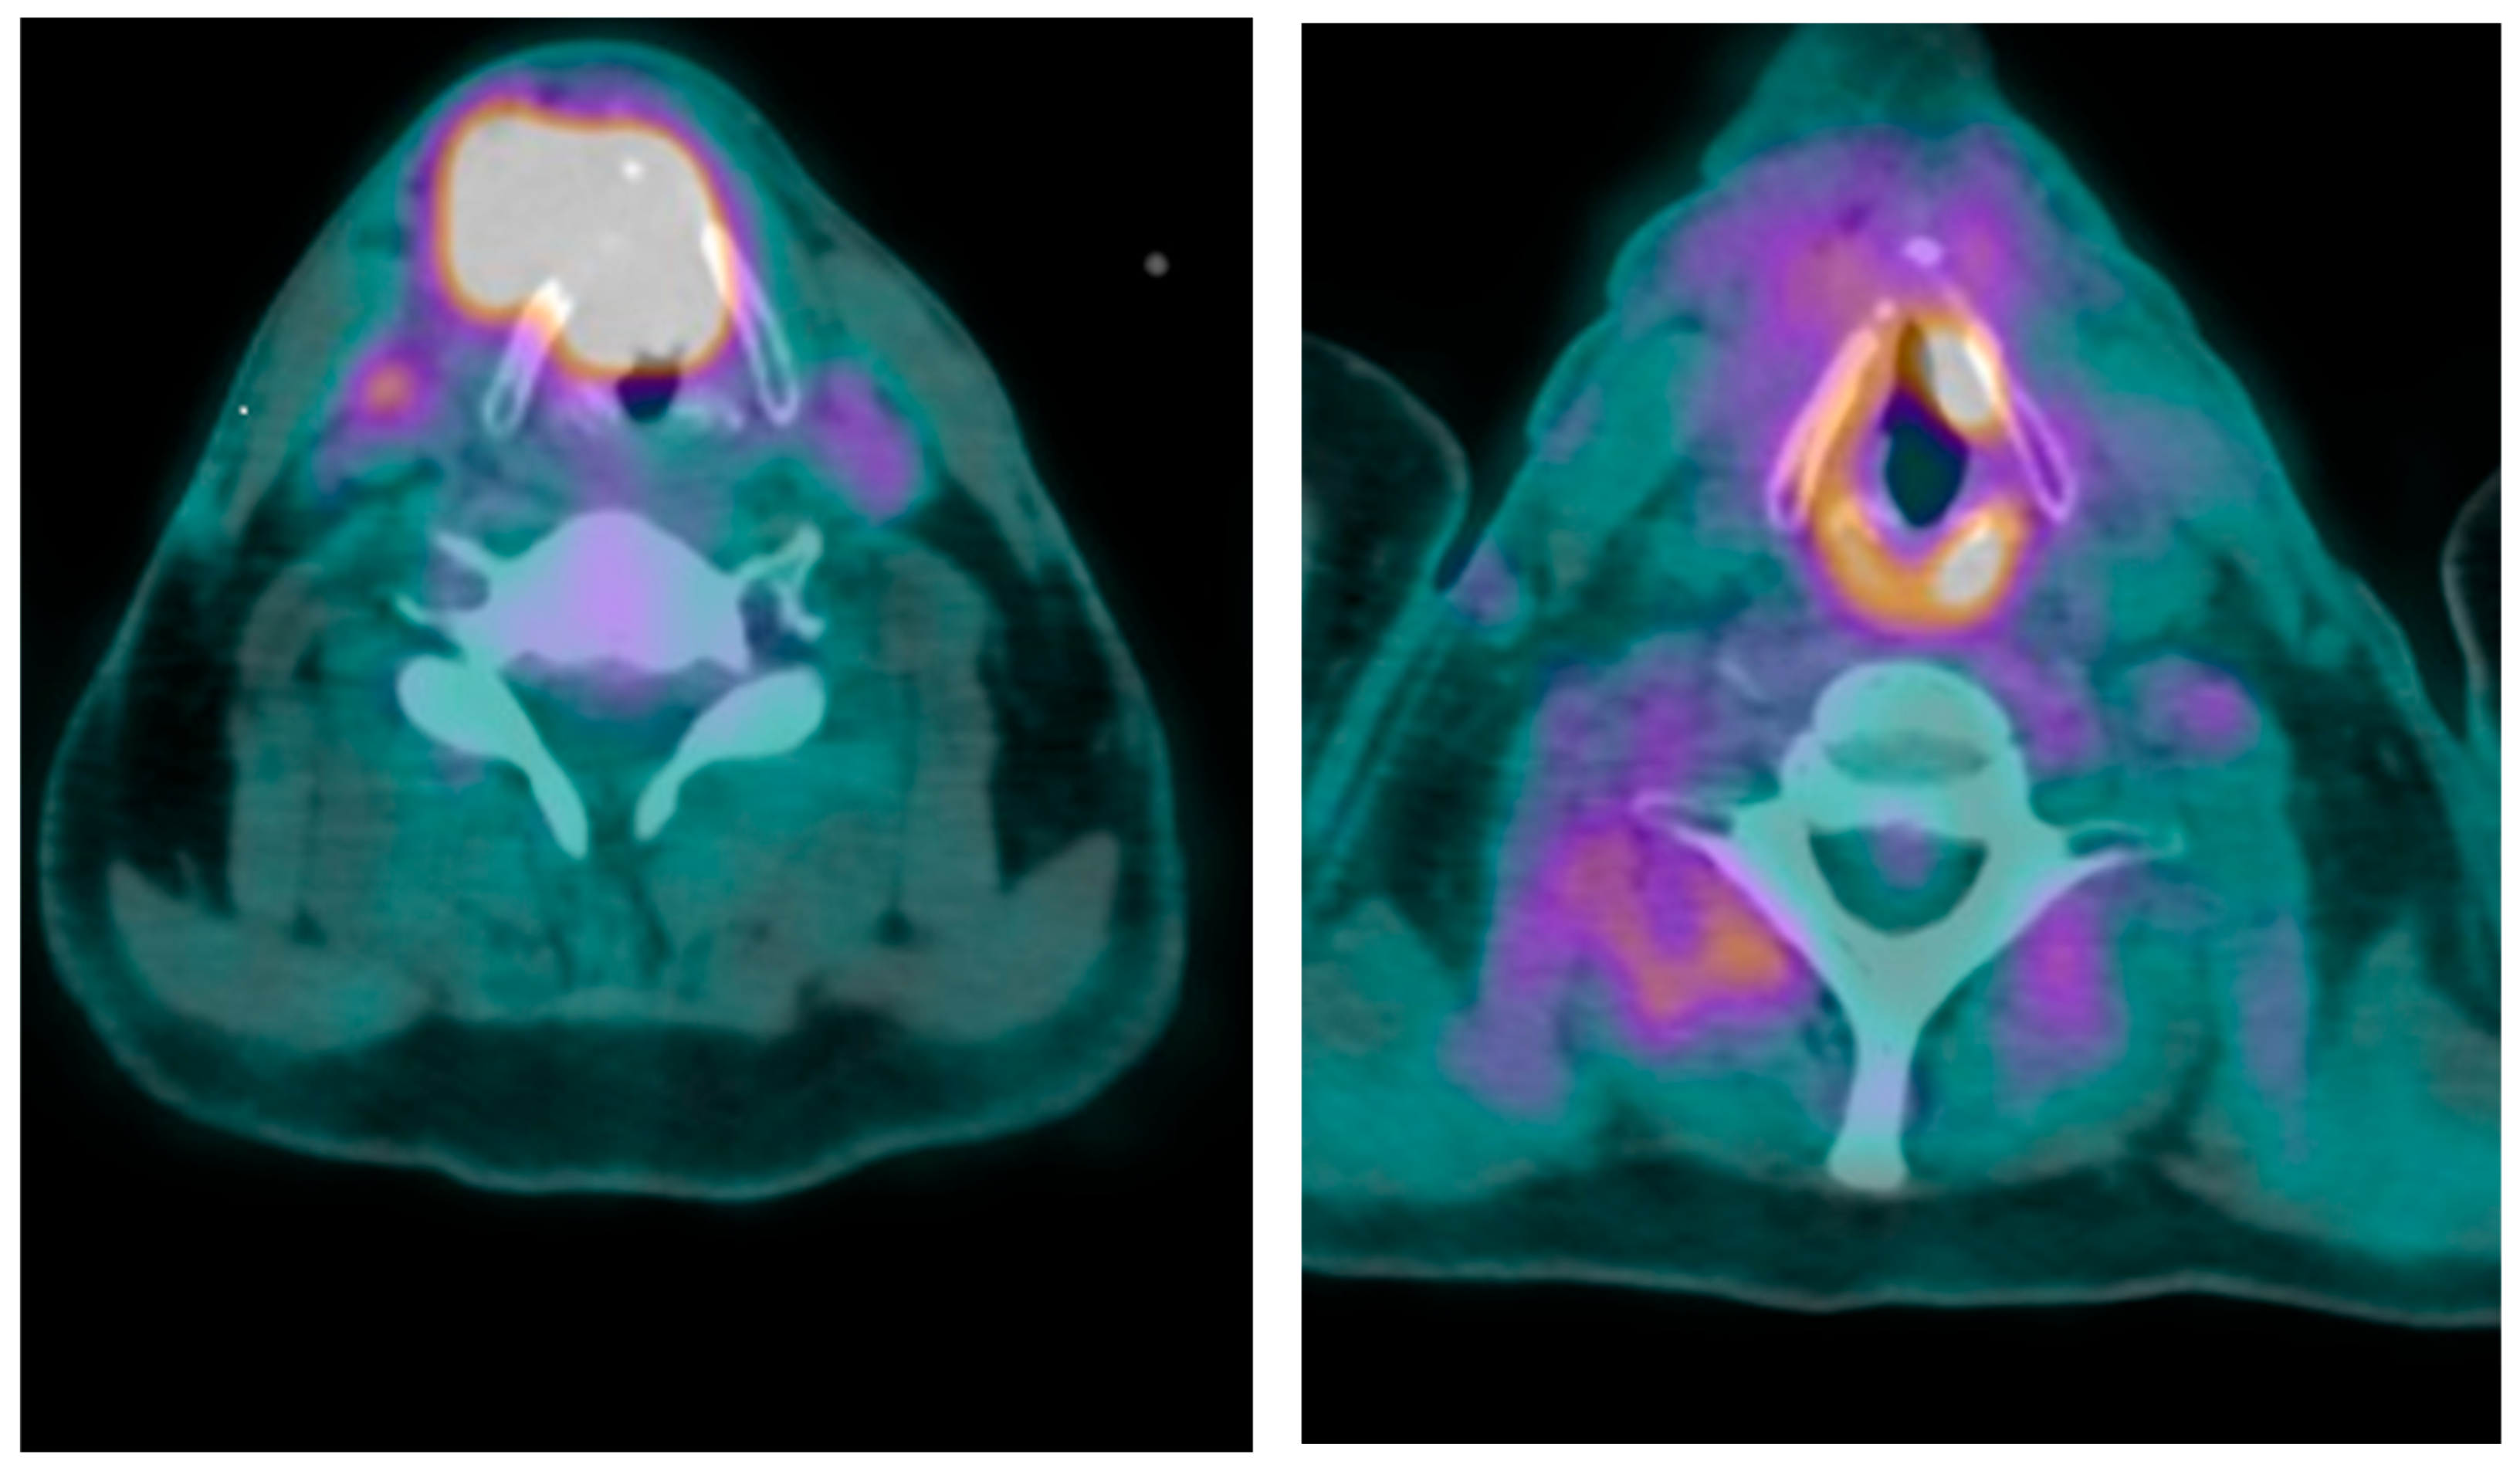

2. Case Presentation